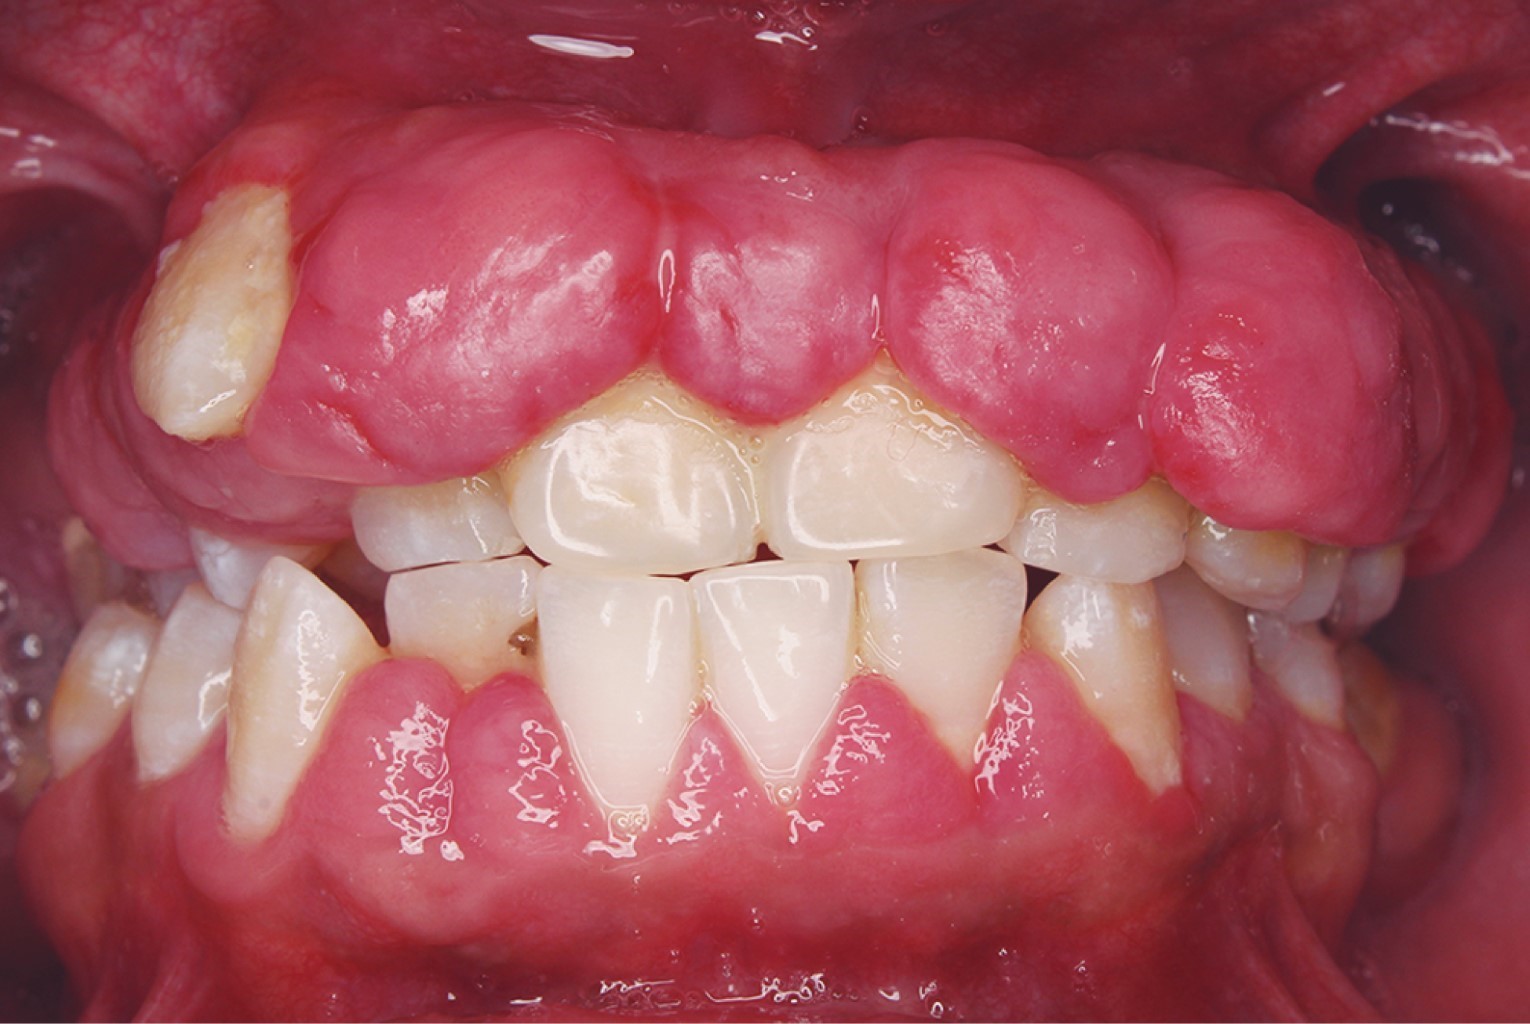

El procedimiento quirúrgico se llevó a cabo bajo sedación y anestesia local. Se inició el detartaje con ultrasonido para disminuir la carga bacteriana en la misma cita debido a la poca cooperación del paciente. Se inició la gingivectomía con electrobisturí y se continuó con hoja de bisturí #15 y tijeras LaGrange (Figura 2).

Figura 2